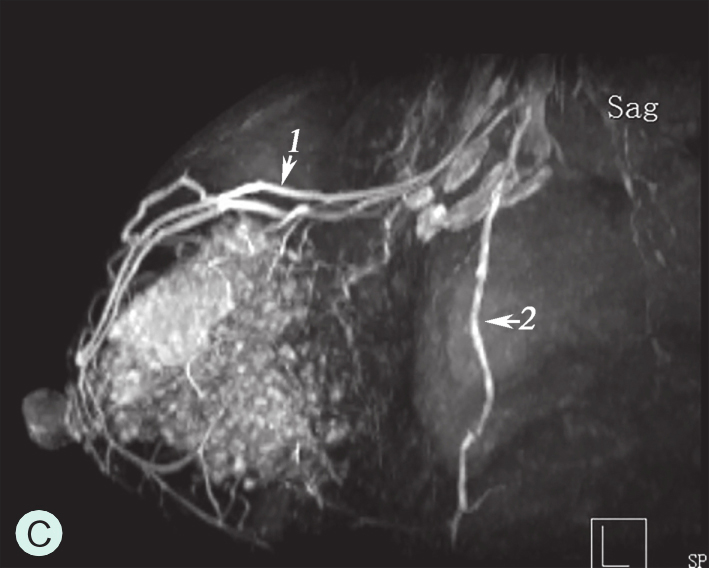

乳腺主要由胸廓内动脉、胸外侧动脉及肋间穿支动脉供血(图1-4-1A~图1-4-1C)。胸廓内动脉发自锁骨下动脉,在相应肋间胸骨旁发出分支穿过胸大肌,主要供应乳房的内侧部分血供;胸外侧动脉发自腋动脉第2段,穿过腋静脉深面,经腋窝沿胸小肌下缘走行,负责胸大肌、胸小肌、前锯肌及乳房外侧部分血供;另外,第3~5肋间动脉从各相应的肋间穿出,与胸外侧动脉及胸廓内动脉分支吻合,供应乳房下部分血供。上述三组主要动脉在乳房内又不断分支并相互吻合形成血管网,且走行自然连续,但缺乏类似于肝脏及肾脏有规律的血管分支树结构,同一女性双侧乳房或不同女性间都不相同,无固定分支规律可循(图1-4-1D)。

图1-4-1 乳腺血供与影像学

A.乳腺血供示意图;B.乳腺增强MRI造影血管图;C.乳腺增强MRI三维重建血管图;D.乳腺血管铸型解剖标本

1.胸廓内动脉;2.腋动脉;3.胸外侧动脉